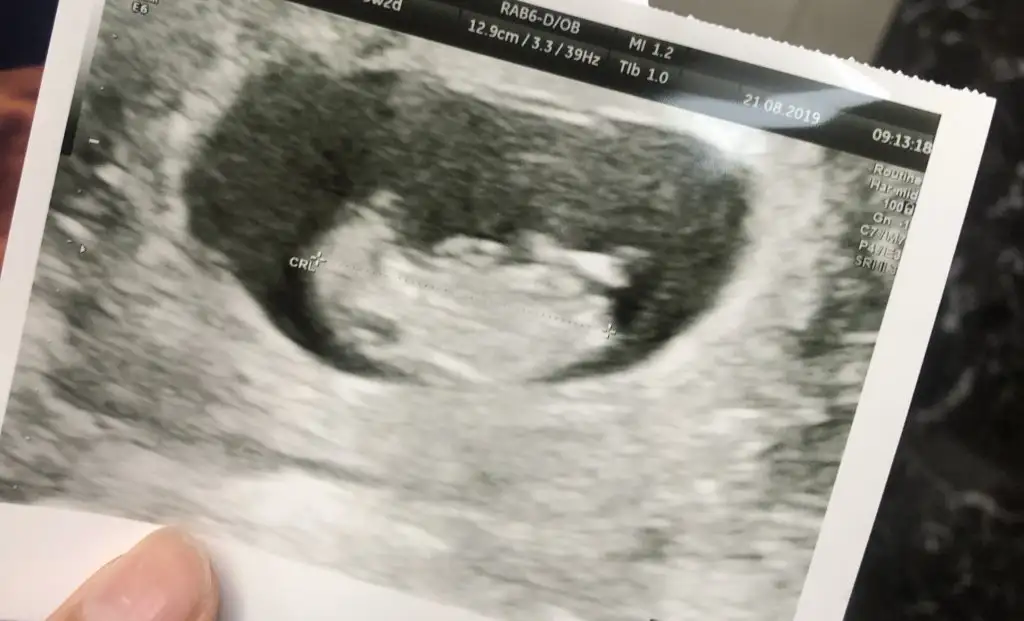

Kaç haftalık bu? İnan ne kafasını ne nubunu görebildim hiç net değil canım.ben bu usg ye bakınca fasulye görüyorum oyyyEki Görüntüle 2300301

Kız dıyorumEki Görüntüle 2300301